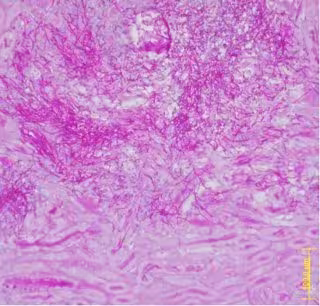

Tinción histológica de un corte de riñon infectado por candida

CNB-CSIC